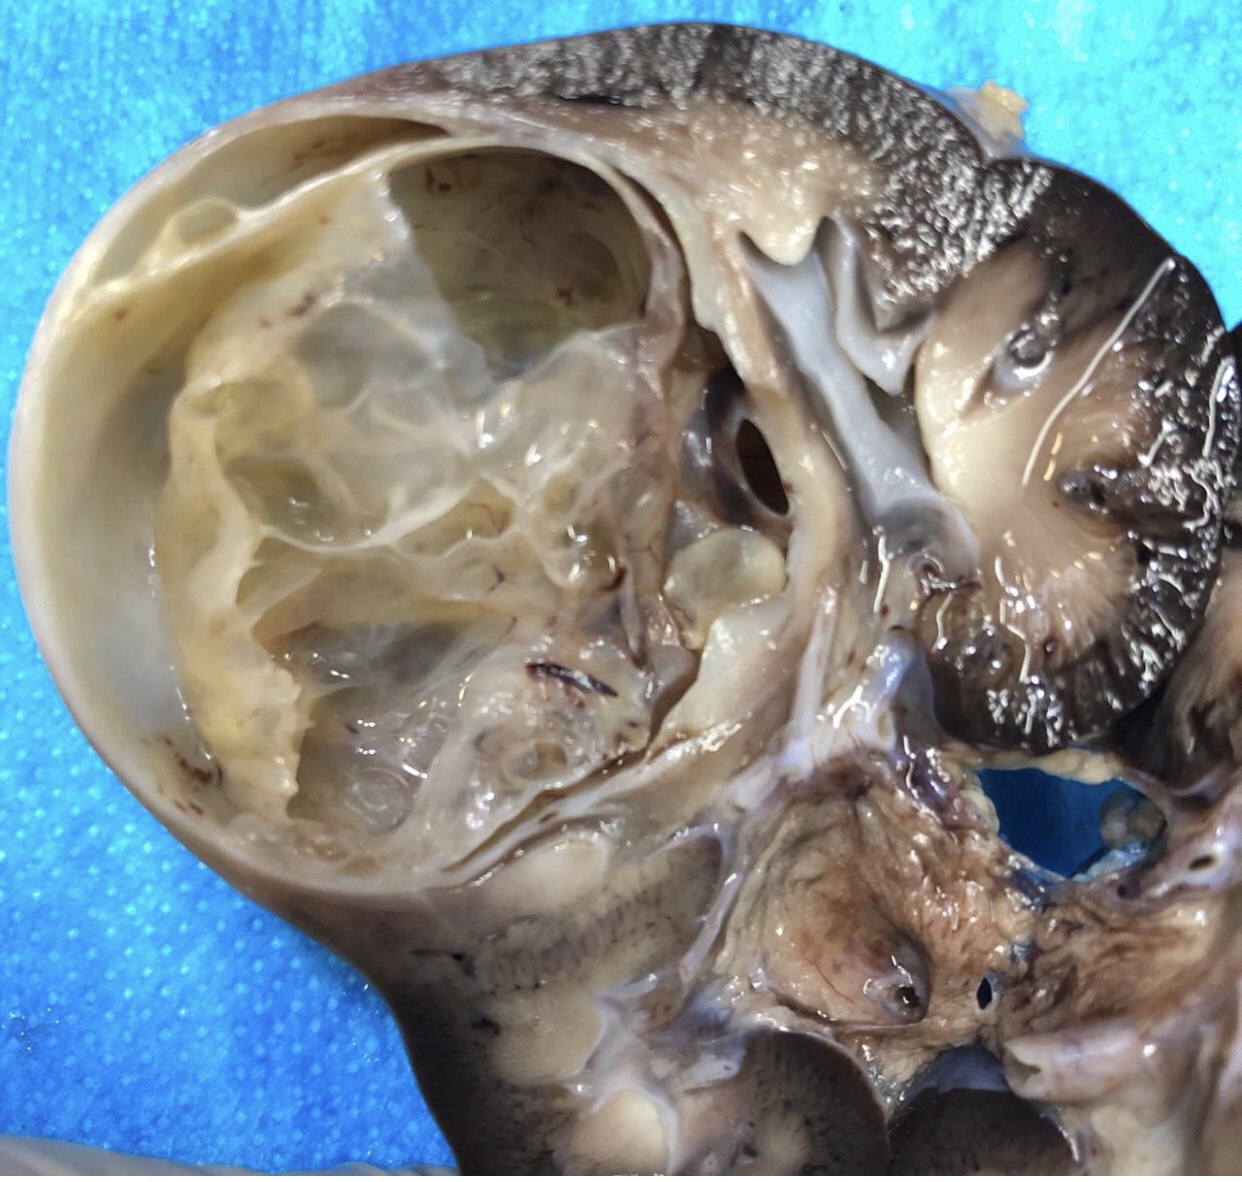

Gross description

- Typically, a large multilocular cystic tumor (mean diameter of 10 cm)

- Thin or variable sized septa

- Well circumscribed

- No expansive nodules

- Reference: J Postgrad Med 2006;52:45

Gross images